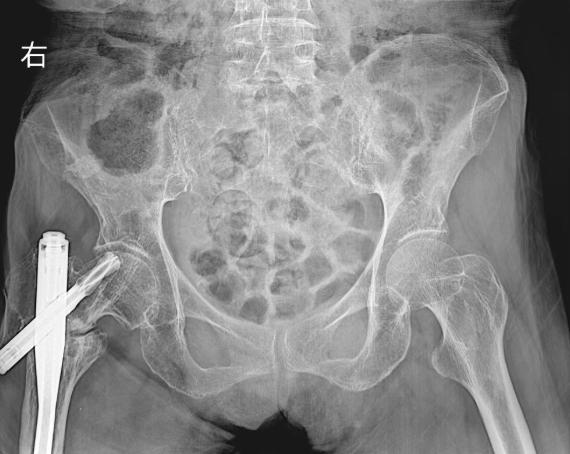

患者化奶奶年近八旬,十二年前因右股骨转子间骨折术后始终未能脱离拐杖,行走困难。近日不慎摔倒导致右侧股骨干再次骨折,且与旧内固定物相互交织,病情极为复杂棘手。面对这一高难度挑战,周口人合医院骨三科在孙杰院长的亲自带领下,迅速启动多学科会诊机制,精准制定了“微创取出原内固定+同期髓内钉复位固定”的一体化手术方案。

术前